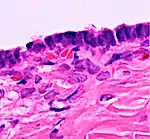

In case an ovarian cyst is surgically removed, a more definite diagnosis can be made by histopathology:

| Type | Subtype | Typical microscopy findings | Image |

| Cystadenoma | Serous cystadenoma | Cyst lining consisting of a simple epithelium, whose cells may be either:[21]

|